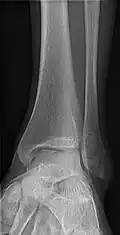

- Ankle - AP/Mortice and Lateral

-

Ankle - frontal -

15 degrees internal rotation -

Lateral (this one a bit suboptimal by not seeing straight through the ankle joint) -

Lateral oblique (to visualize the posterior border of the tibia)